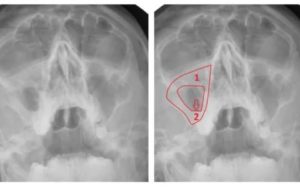

Также при пристеночном гайморите пациента обязательно направляют на рентген. Вот, что позволяет выяснить этот способ:

- Снижение пневматизации верхнечелюстного синуса.

- Состояние орбит глаз и лицевых костей.

- Пристеночное затемнение пазух.

Обычно после проведения рентгена никаких вопросов не остается. Но, если ситуация все еще остается не проясненной, назначают проведение компьютерной томографии. Это очень информативный метод диагностики. Благодаря КТ удается в деталях рассмотреть все структурные изменения пазух, выявить воспаление, уплотнение, деформацию и т. д.

- Пристеночное затемнение на снимке. Его можно заметить на рентгенограмме. Для подтверждения диагноза снимки делают минимум в двух проекциях. Разросшийся эпителий напоминает темные асимметричные пятна. Помимо этого, применяют КТ и МРТ.